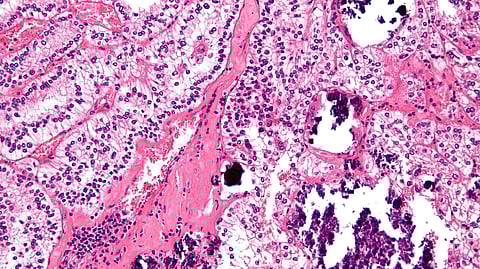

To answer these questions, Drs. Sabari, Lyons, and Pradhan and their colleagues examined tRCC cells from patients treated in UTSW’s Kidney Cancer Program, kept in a biorepository led by study co-author James Brugarolas, M.D., Ph.D., Professor of Internal Medicine and the program’s Director. Using a special stain, they saw that the oncofusion proteins formed biomolecular condensates – dynamic networks of different proteins that segregate themselves within cells – but the “wild-type” (not mutated) TFE3 protein did not. These results suggest that a common feature of the seemingly random fusion partners is the ability to form condensates.